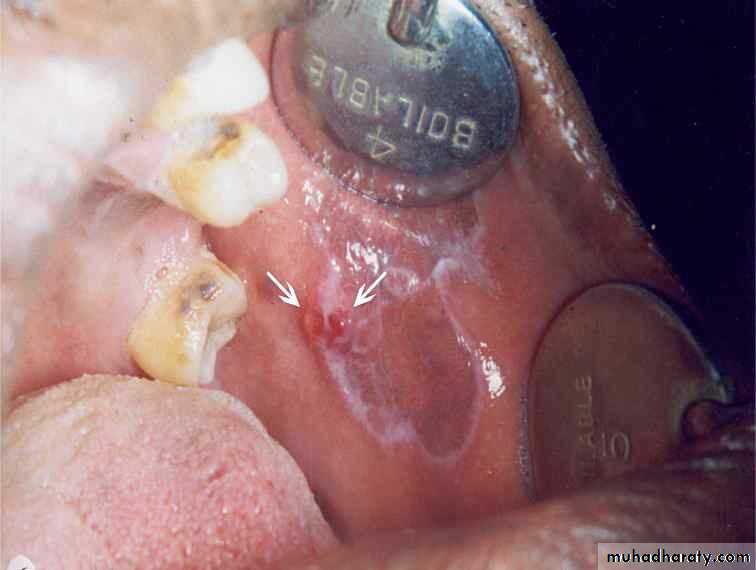

• 2. Speckled• Leukoplakia:

•

• •

• Mixed red & white

• Keratotic nodules on atrophic red base

• High malignant transformation